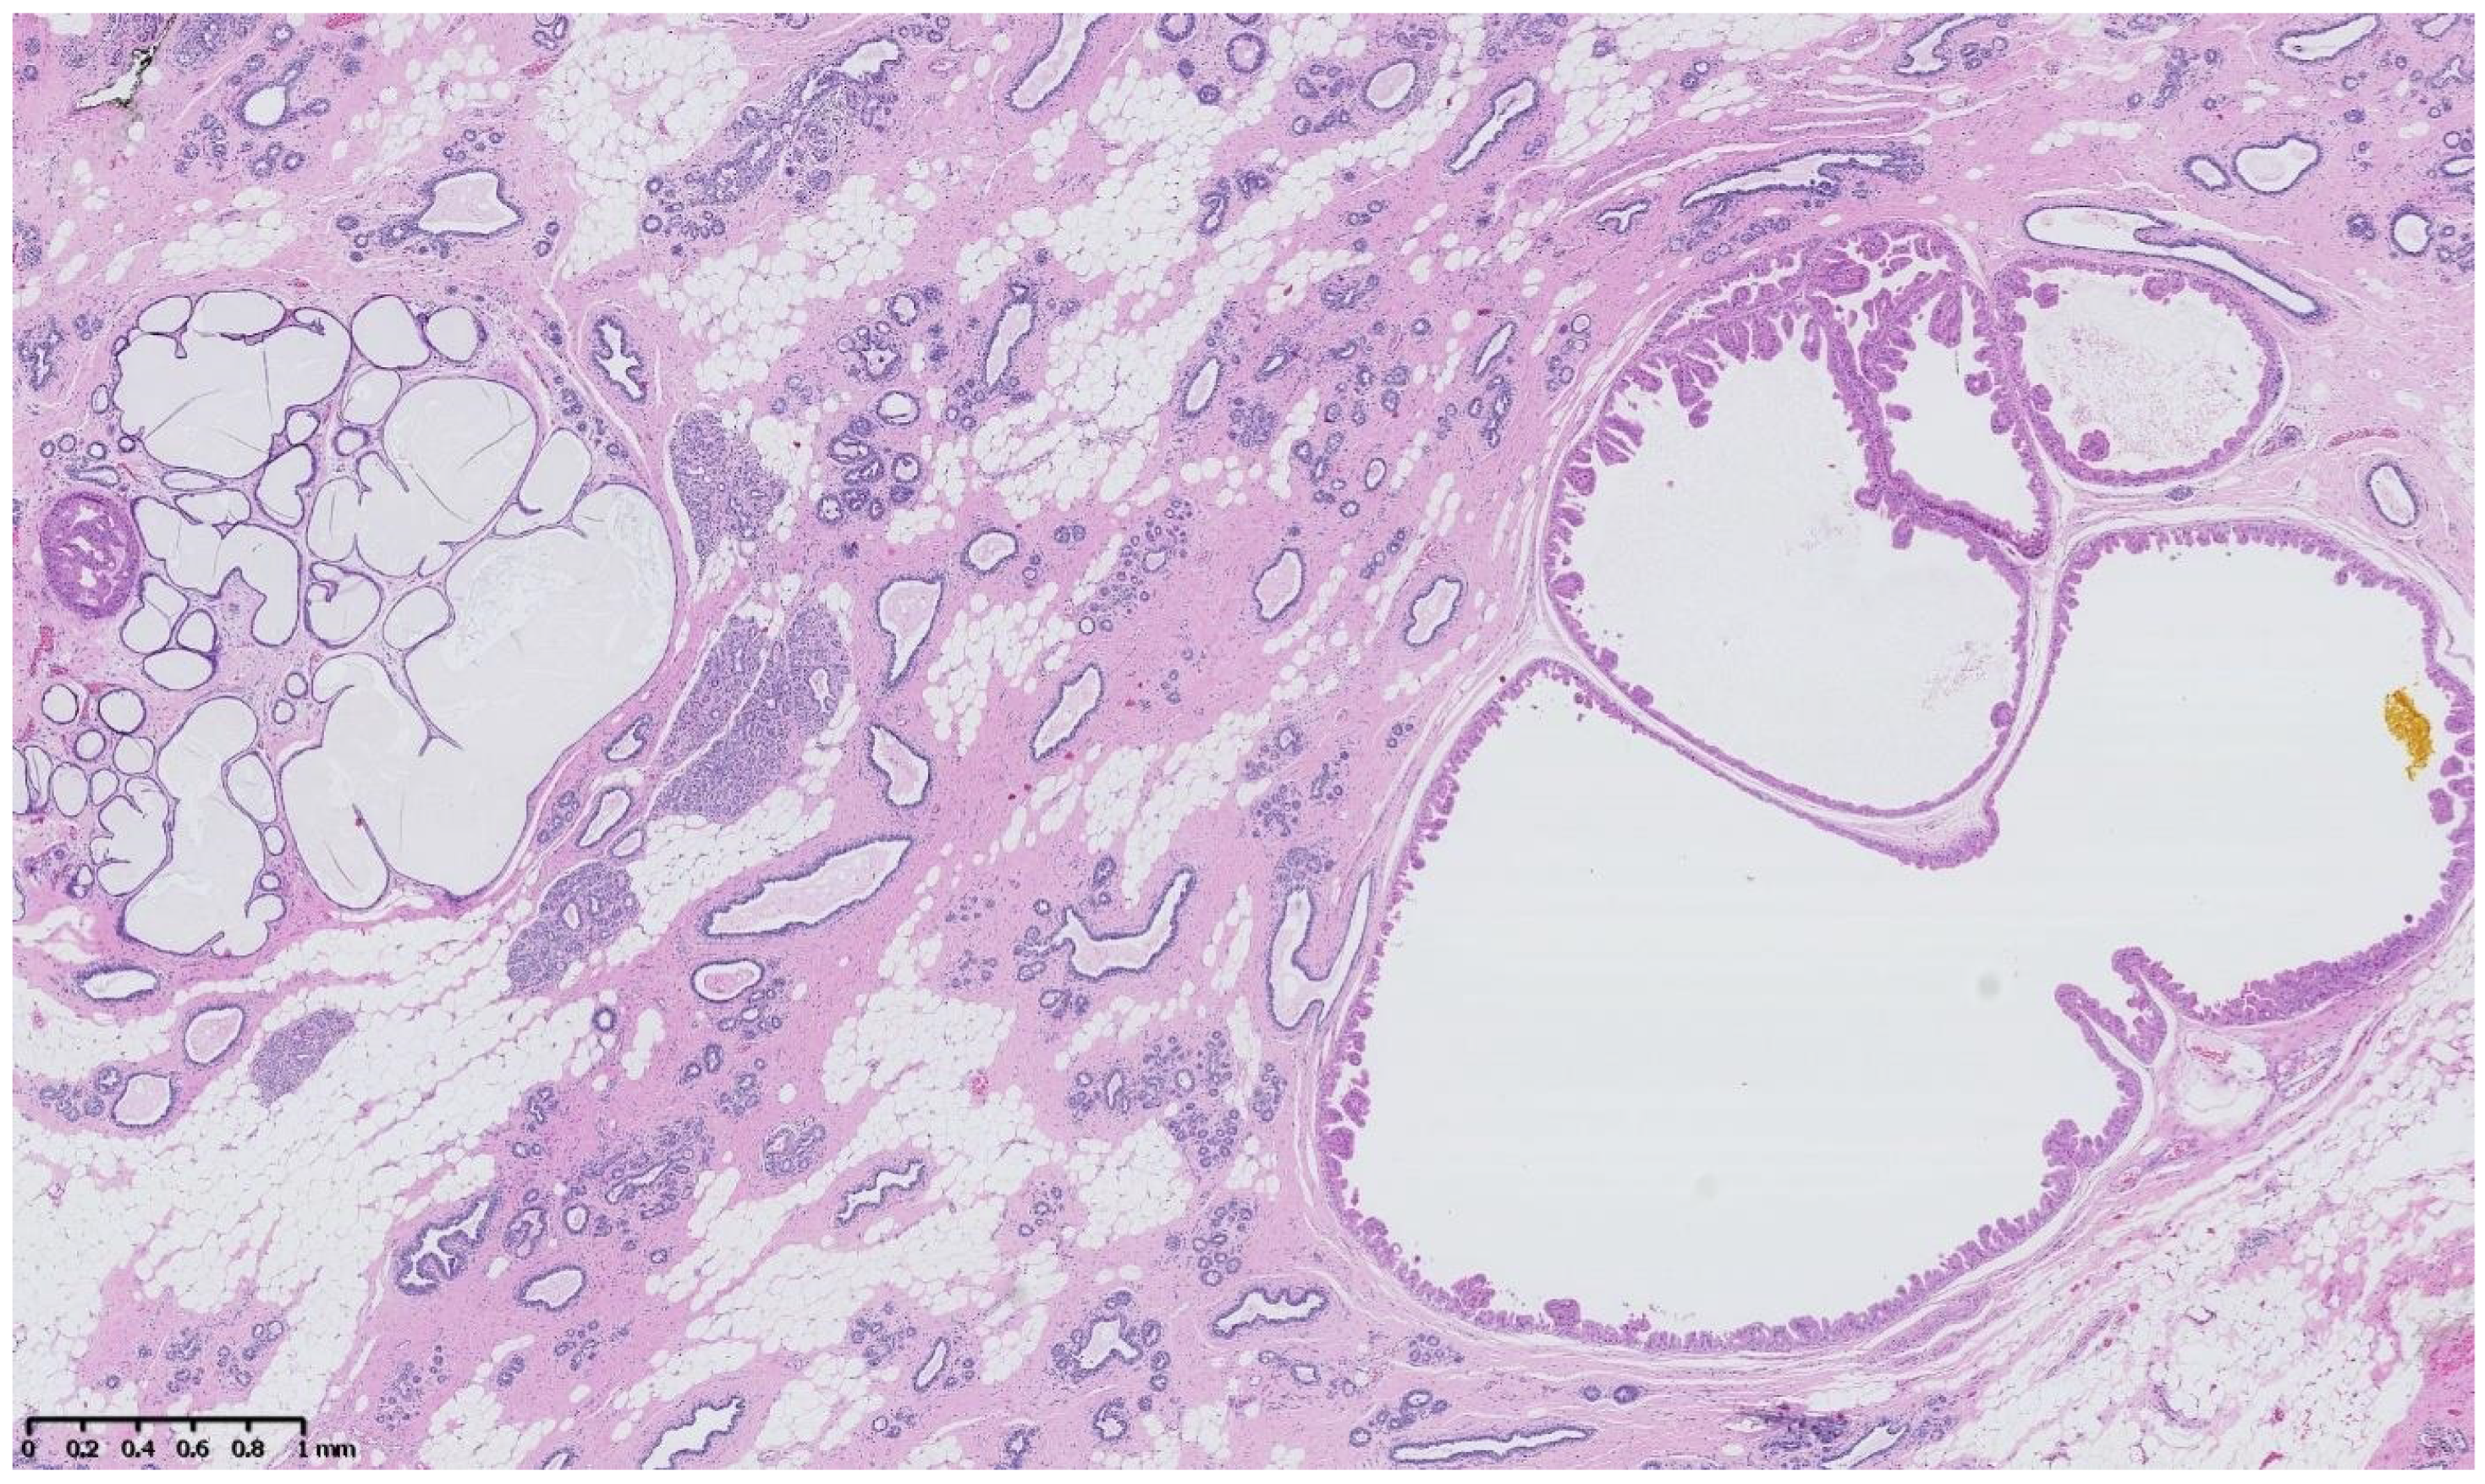

Figure 2, Figure 3, Figure 4, Figure 5, Figure 6 and Figure 7 describe a panel of different lesions observed in a patient treated for 2 years by natural estrogens and antiandrogens.

Figure 2.

Hematoxylin and eosin staining: the surrounding breast parenchyma shows fibro-cystic changes with apocrine metaplasia, cystic ducts and usual duct hyperplasia.